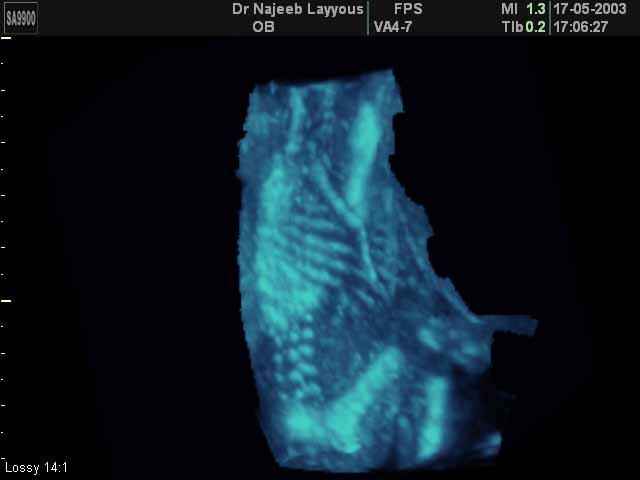

- 3D Photos échographie du squelette du fœtus